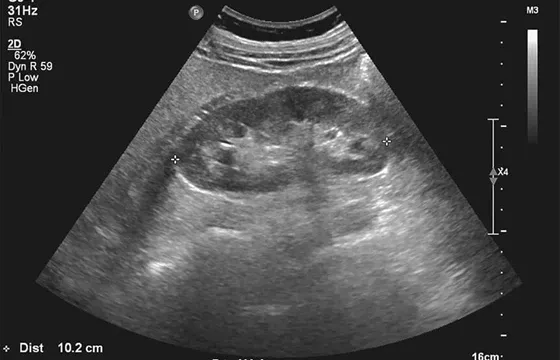

Obraz wewnątrz ciała: kiedy wykonuje się USG, TRUS lub tomografię?

Badania obrazowe pozwalają lekarzowi zajrzeć do wnętrza Twojego ciała i ocenić strukturę narządów. Najczęściej wykonywane jest USG układu moczowego, które pozwala ocenić nerki, pęcherz moczowy, a u mężczyzn także prostatę. Jest to badanie nieinwazyjne i bezbolesne. W celu dokładniejszej oceny prostaty u mężczyzn może być zlecone USG przezodbytnicze (TRUS), które dostarcza bardzo szczegółowego obrazu gruczołu. W bardziej skomplikowanych przypadkach, gdy potrzebny jest jeszcze dokładniejszy obraz, urolog może zlecić tomografię komputerową (TK) lub rezonans magnetyczny (MRI), szczególnie w diagnostyce nowotworów czy kamicy.